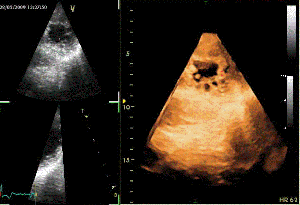

Για σύγκριση, οι εικόνες CTA\ECG πριν την τοποθέτηση της συσκευής:

Και στο ηλεκτροφυσιολογικό εργαστήριο:

<στην επόμενη καταχώρηση, θα δείτε και τις εικόνες TEE>